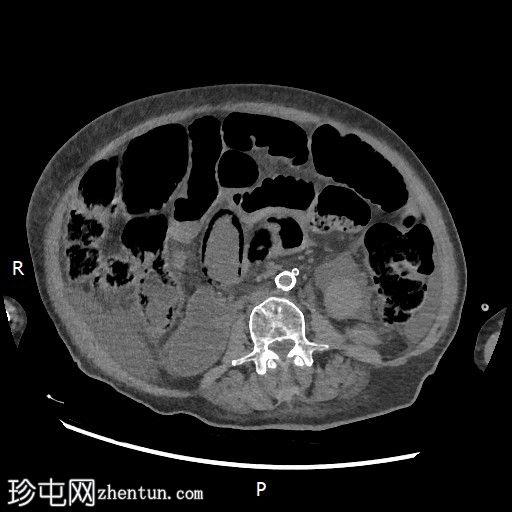

冠状位增强扫描(门静脉期)

大肠内可见中度粪便。横结肠轻度扩张(约6.6厘米)。

数处小肠袢直径接近临界值(约3厘米),部分肠袢内可见粪便。

腹部中央及右侧可见数处小肠袢肠壁明显变薄,并可见肠壁积气。

少量腹水。

主动脉及其内脏分支可见明显动脉粥样硬化。肠系膜上动脉(SMA)开口处中度至重度狭窄;但开口后显影良好。

目前未见明显的门静脉-肠系膜静脉积气。

无气腹。